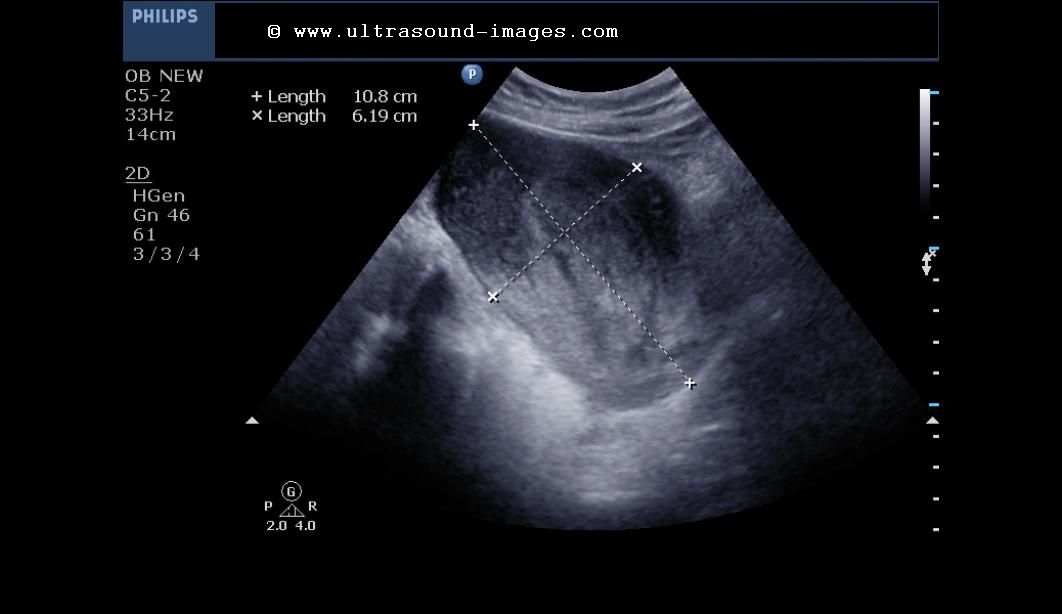

From www.youtube.com

Ultrasound Pregnancy retained product of conception. Vaginal bleeding. YouTube What Do Retained Products Of Conception Look Like Should consider abnormal if heavy or last >3 weeks. Retained products of conception (rpoc) refer to the persistence of placental and/or fetal tissue in the uterus following delivery, termination of pregnancy or a miscarriage. Retained products of conception (pocs) can occur after spontaneous or induced abortion and after delivery. Retained products of conception (rpoc) generally result after first half of. What Do Retained Products Of Conception Look Like.